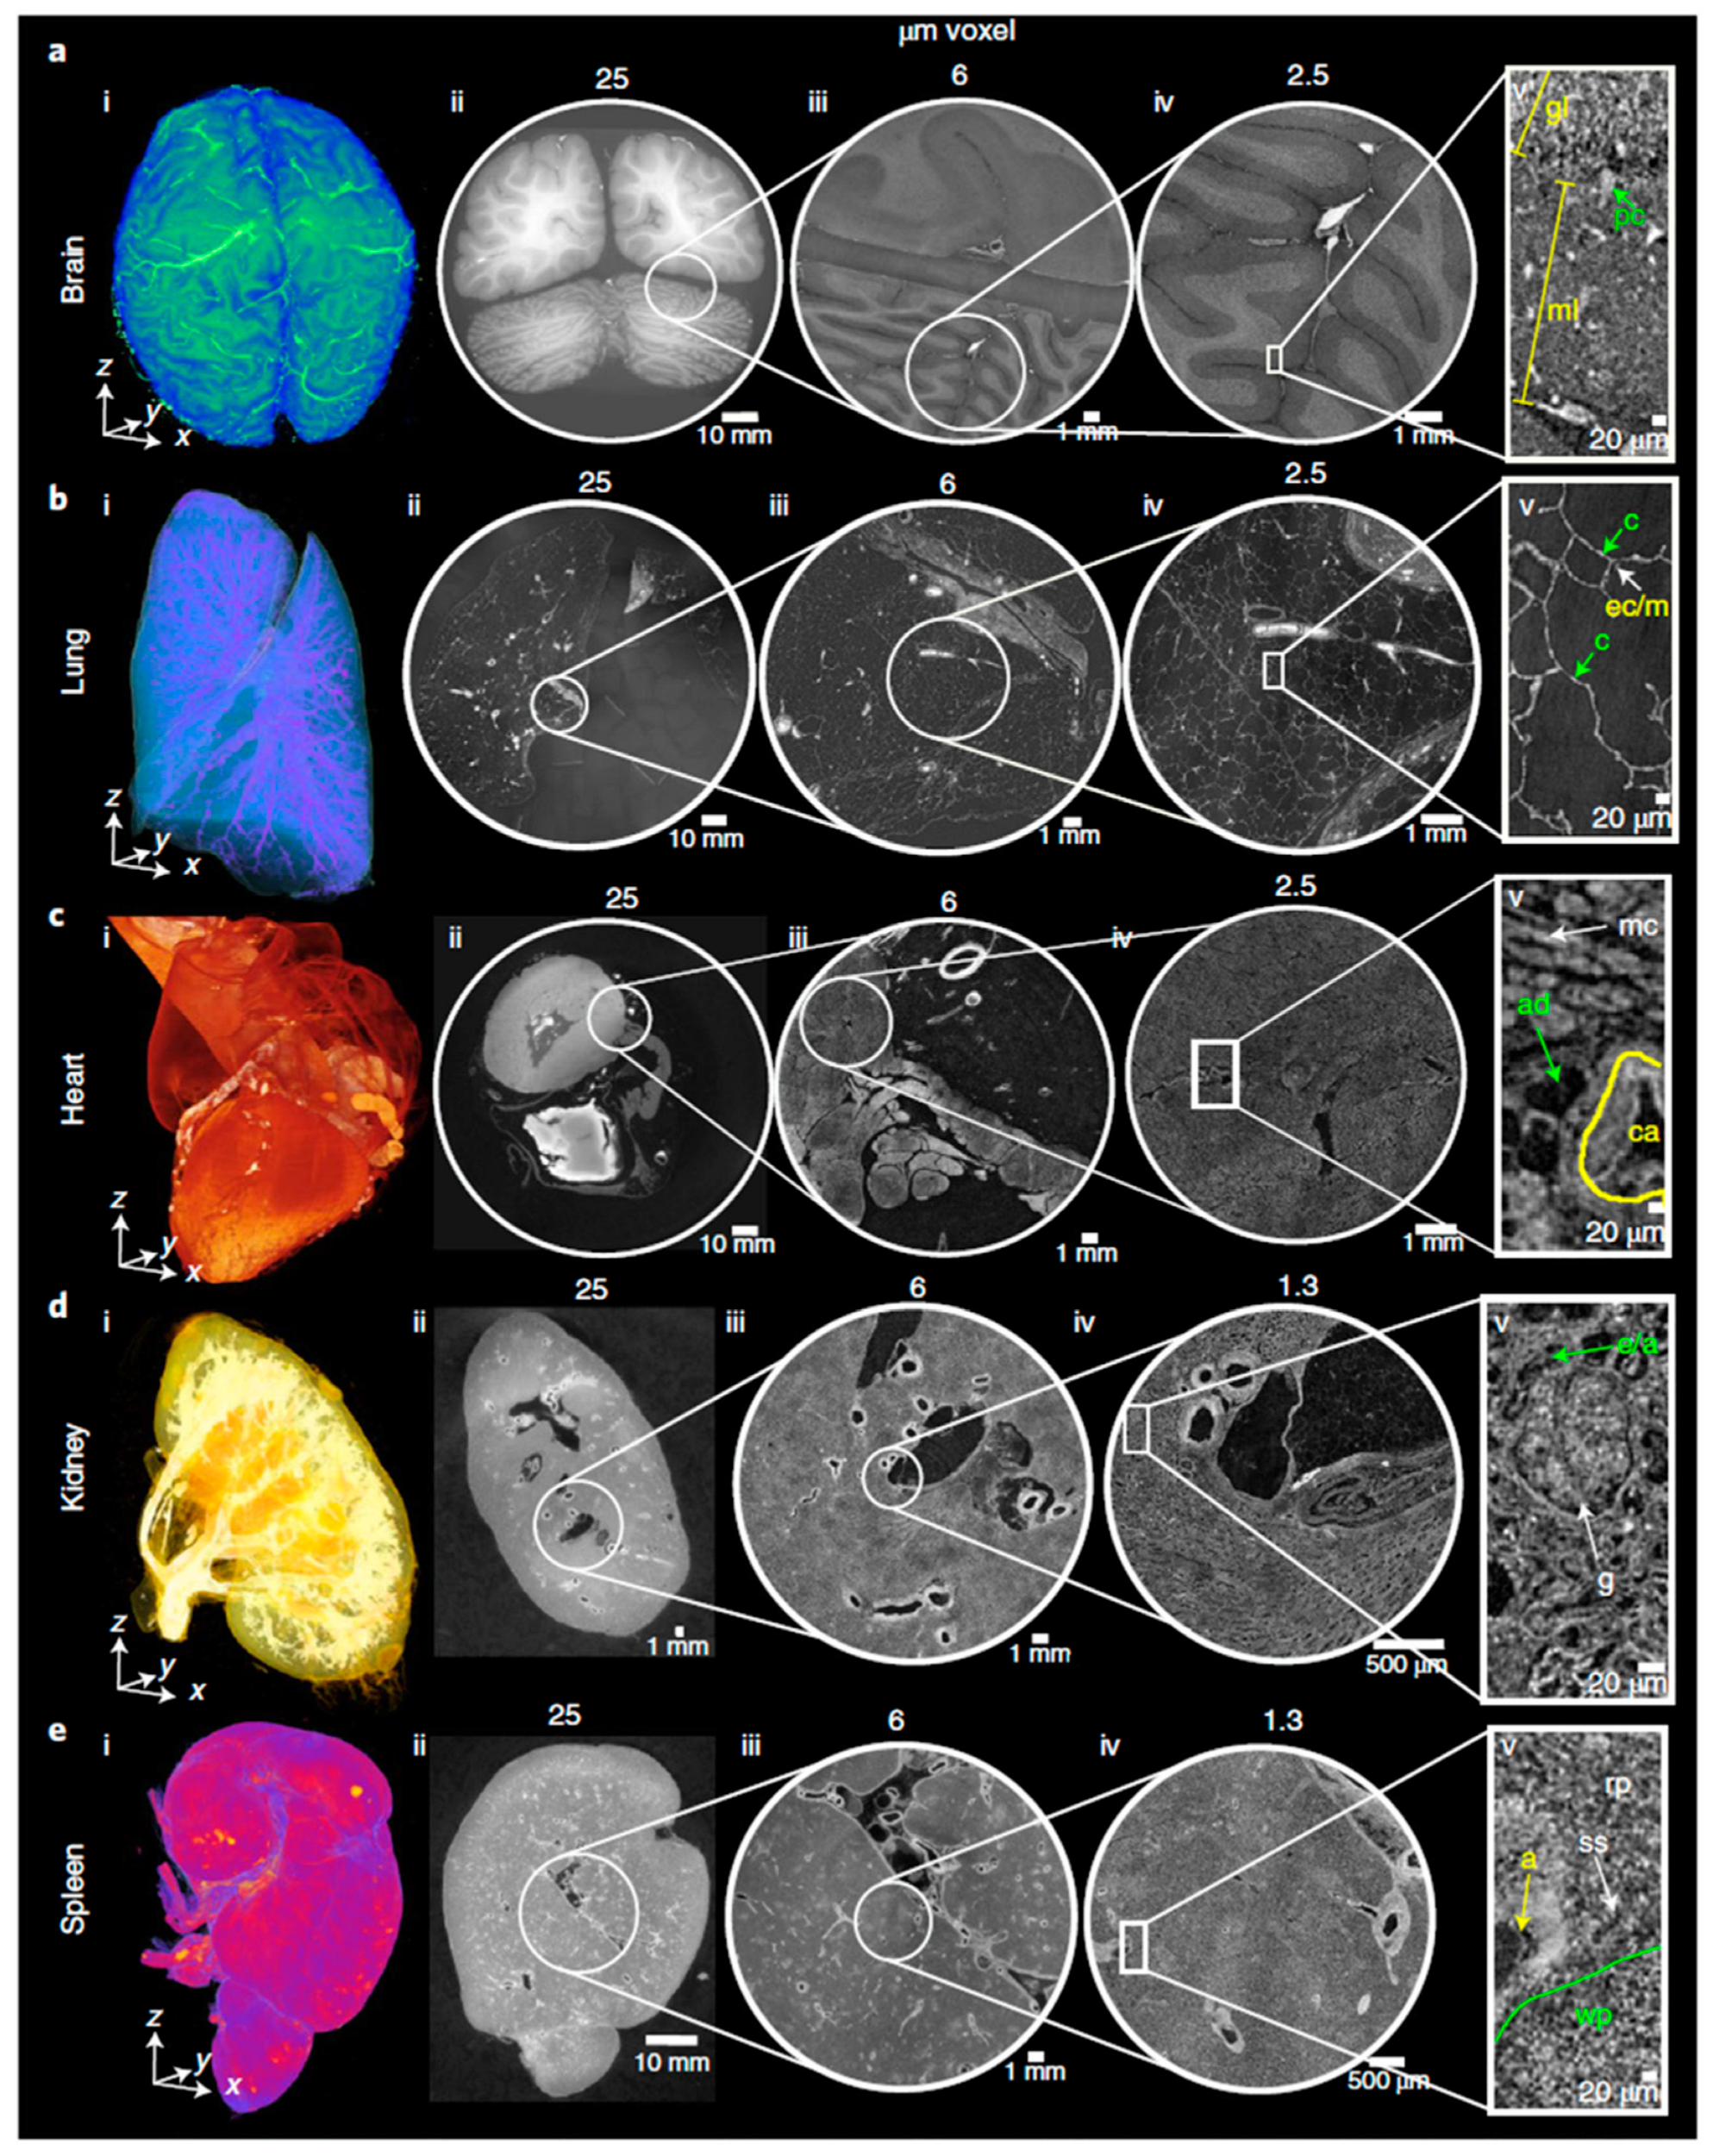

3.5. Organ to Cellular Scale Imaging

- Walsh, C.L.; Tafforeau, P.; Wagner, W.L.; Jafree, D.J.; Bellier, A.; Werlein, C.; Kuhnel, M.P.; Boller, E.; Walker-Samuel, S.; Robertus, J.L.; et al. Imaging intact human organs with local resolution of cellular structures using hierarchical phase-contrast tomography. Nat. Methods 2021, 18, 1532–1541. [Google Scholar] [CrossRef]